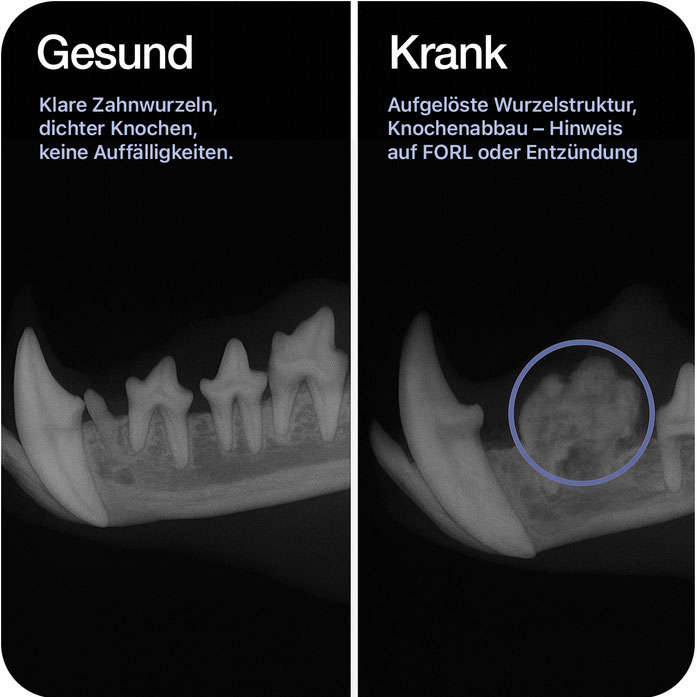

Zahnröntgen

Präzise Darstellung von Zahnwurzel, Kiefer und Zahnhalteapparat – für eine sichere Diagnose

Typische Einsatzbereiche

• Erkennung von FORL (feline odontoklastische resorptive Läsionen)

• Untersuchung von Zahnwurzeln, Entzündungen oder Abszessen

• Beurteilung des Kieferknochens und Zahnhalteapparates

• Kontrolle nach Zahnextraktionen oder Verletzungen